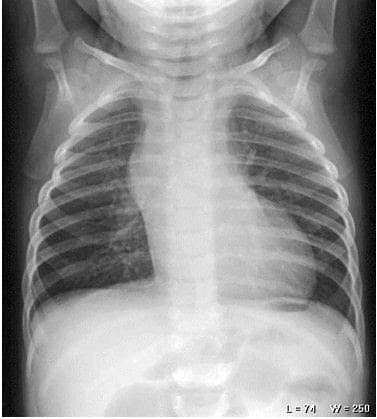

Hình ảnh chụp x quang phổi ở trẻ em

Chụp X-quang là một kỹ thuật chẩn đoán hình ảnh có sử dụng tia X – chùm tia bức xạ có năng lượng cao được phát ra từ máy chụp x-quang (còn gọi là chụp X Ray).

Các tia X này sẽ đi xuyên qua các mô mềm và các thành phần dịch trong cơ thể, hình ảnh sẽ được thu lại. Từ đó các bác sĩ có thể chẩn đoán bệnh lý và đưa ra hướng điều trị hoặc các chỉ định khác cần thiết cho bệnh nhân.